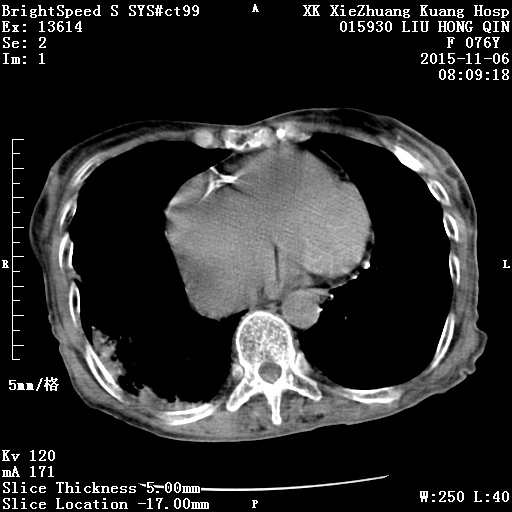

CT51290:腹痛

冠心病,心绞痛,急支,阵发性腹痛。门脉及下腔静脉这么宽正常吗?

肝内血管扩张,肝肾间隙见低密度影,心脏增大,右冠脉钙化,心包及右侧胸膜增厚,子宫内见多发钙化,膀胱内见导尿管影。考虑:肝肾间隙积液?子宫肌瘤钙化?建议增强或MRI检查。

左下腹盆腔占位伴钙化,边界不清,考虑卵巢癌可能,建议增强或核磁